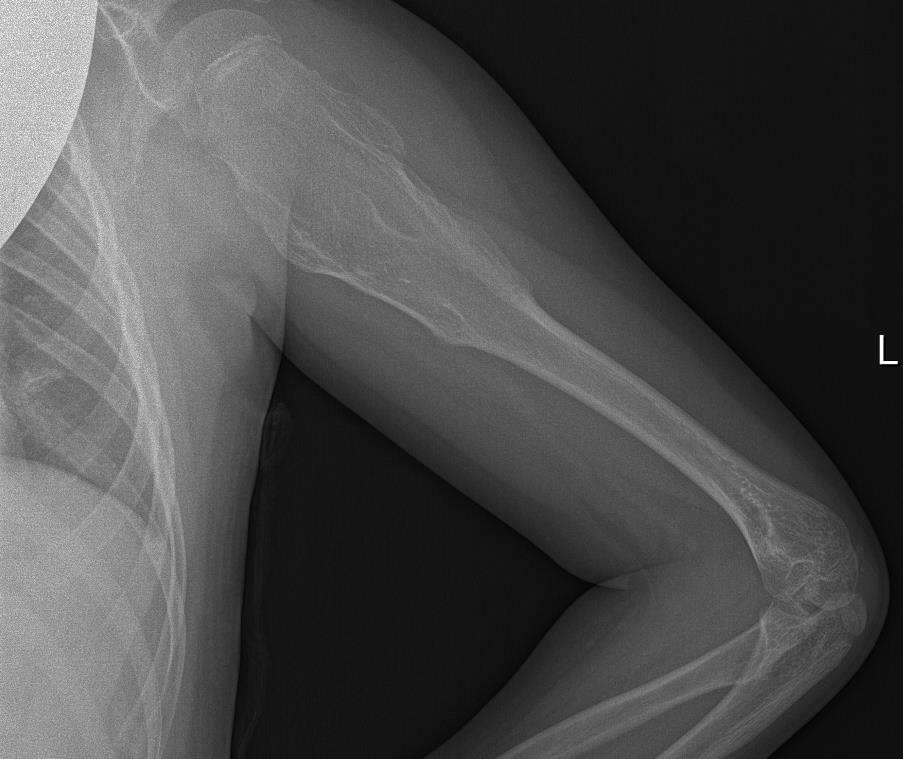

Radiografía de Miembro superior izquierdo: Se visualiza lesión lítica metafiso-diafisaria en húmero izquierdo expansiva con excrecencias óseas y margen estrecho con hueso sano.

Tras visualizar alteración en la ecografía del centro de salud, se deriva a radiología para realizar ecografía reglada y completar estudio con radiografía, así como realizar derivación para valoración por parte de Traumatología del Hospital Santa Lucía.